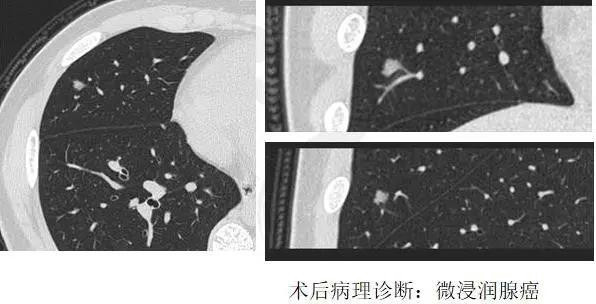

13歲男生小周,因為和同學之間起爭執(zhí)導致胸部受創(chuàng),后因胸部疼痛來衢州市人民醫(yī)院急診就診,經胸部CT檢查,發(fā)現小周的右肺有一6mm左右的微小陰影,經放射科診療團隊識別,高度懷疑小周的肺部陰影性質不一般,經與小周家人溝通后,小周接受了微創(chuàng)手術,術后病理確診為:微浸潤腺癌。一場意外發(fā)現了隱藏在身體里的巨大隱患,小周無疑是幸運的。這么小的孩子,這么小的病灶,現在就能夠作出精確的診斷,在以前是不可想象的,這樣的進步得益于影像團隊幾年來的努力攻關。